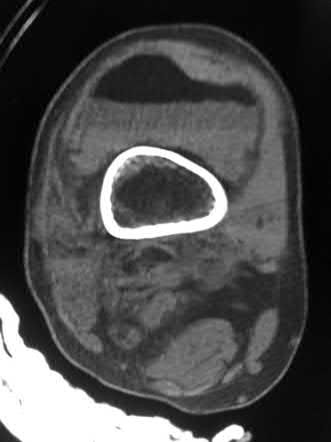

A 38-year-old male suffers the injury shown in Figure A. During operative fixation, free osteoarticular fragments are encountered and reconstruction of these pieces is attempted. Postoperatively, which of the following will have the most beneficial effect on the healing potential of the surviving chondrocytes within these reconstructed articular segments?

Figure A demonstrates a comminuted tibial plateau fracture with significant intra-articular involvement. Basic science evidence has demonstrated that post-operative gentle compressive loading may have a positive impact on articular cartilage healing; however, excessive shear loading may be detrimental.

Irrgang et al provide guidelines for rehabilitation following surgical management of articular cartilage lesions of the knee. They state that after articular cartilage repair, exercises to enhance muscle function must be done in a manner which minimizes shear loading of the joint surfaces in the area of the lesion. The authors also discuss the benefits of gentle compressive loading and motion of the joint, and its positive effects on chondrocyte nutrition.

Furthermore, they recommend a period of protected weight bearing as often being necessary, and that this should be followed by progressive loading of the joint.

Illustration A is a diagram showing the different layers of joint cartilage.